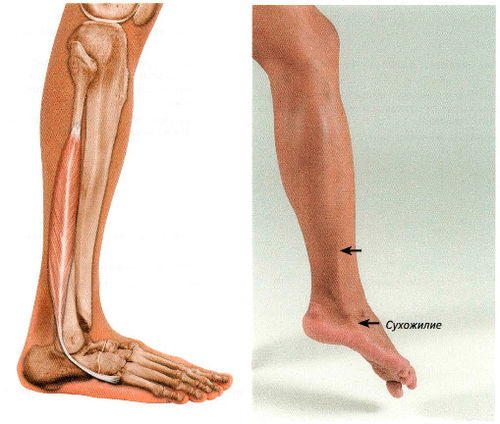

Анатомия подошвенной мышцы голени: подробное рассмотрение